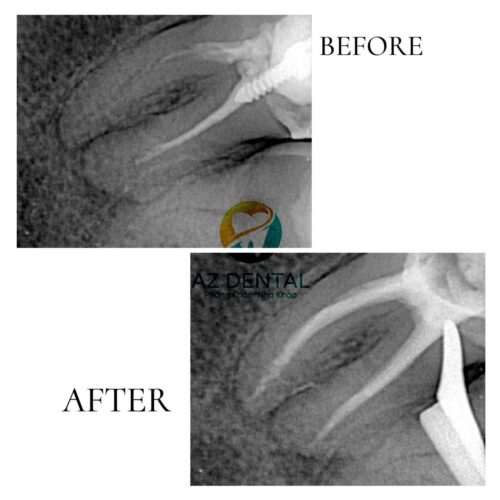

October 5, 2024✅Một đồng nghiệp đã có 2 răng chữa tủy cách đây 10 năm lúc còn chưa học Trường Y

👉Sau khi biết vấn đề răng mình đã điều trị tủy chưa tốt cách đây 10 năm nên luôn mong muốn điều trị lại vì sợ nhiều vấn đề về sau

✅Đội ngũ Bác Sĩ Bên AZ Dental đã dùng tất cả các máy móc và vật liệu để lấy thuốc cũ trong ống tủy ra và đặt lại một loại thuốc tương thích sinh học tốt hơn đồng thời cũng làm kín các ống tủy còn lại để đảm bảo hạn chế nhiễm trùng sau này !

🔴Mất gần 7 tiếng đồng hồ để điều trị lại cho 2 răng của Bác Sĩ này vì Bác từ Lâm Đồng lên không đi lại được nhiều lần điều đặc biệt Bệnh Nhân Này Cũng Chính là Bác Sĩ Răng Hàm Mặt mà AZ Dental thực hiện và còn nhiều ca khác AZ Dental xin chia sẻ ở nhiều bài sau nhé ạ !